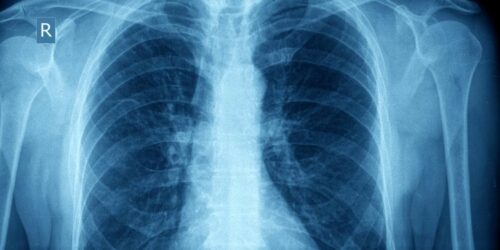

Possible Complications of Asthma

Asthma is a condition that affects an estimated 300 million people across the globe. There are a number of complications that can arise for asthma patients. Some of these include- Increased risk of infections such as pneumonia or influenza. Decreased quality of life due to poor management of the condition.